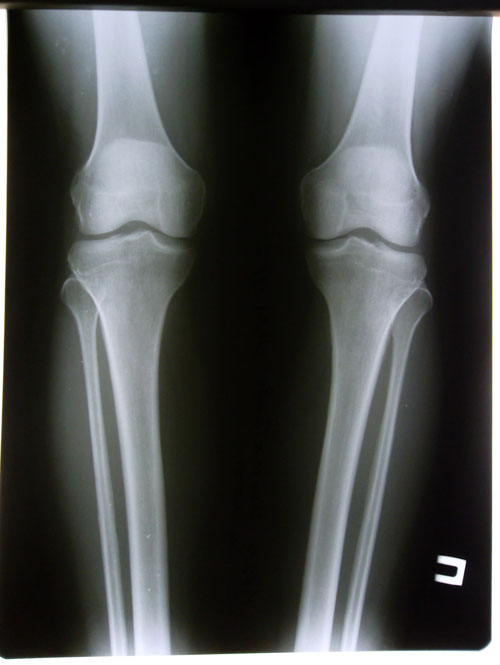

Дата операции 16.06.2014г.

Дата снятия аппаратов 04.11.2014г.

Срок лечения 138 дней.

рентген в день снятия аппаратов.

ортопедическая ось до операции

ортопедическая ось после исправления о - образной деформации